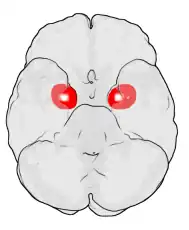

Hay evidencias en muchas especies de que la amígdala está muy involucrada en la respuesta a las hormonas sexuales. La amígdala contiene receptores tanto para estrógenos como andrógenos y responde a fluctuaciones en los niveles hormonales mediante cambios en su morfología. La amígdala es mayor en varones adultos tanto en humanos como en muchos roedores y las hormonas parecen ser capaces de alterar muchas características de la amígdala, incluidas el número de neuronas y la expresión de sus neurotransmisores.

Además, resultados recientes sugieren que las diferencias sexuales en la amígdala podrían correlacionarse con diferencias hemisféricas de la amígdala. Cahill y otros[6] sugieren una teoría «derecha-varón, izquierda-mujer» de la actividad de la amígdala. Así, las conexiones con la amígdala derecha facilitan un mejor seguimiento o vigilancia de estímulos externos, y las conexiones con la amígdala izquierda facilitan un mejor seguimiento o vigilancia de estímulos internos.